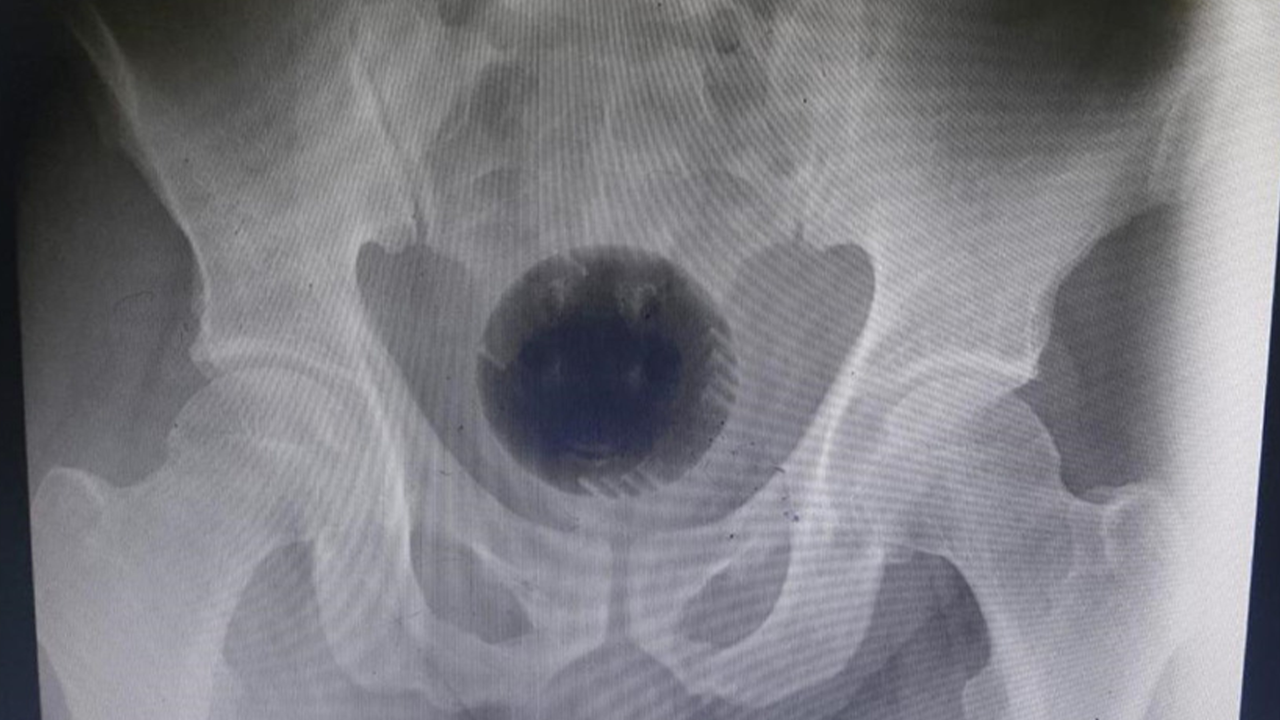

As reported by Daily Mail, the man was rushed to the hospital by his wife after the plastic ball, which was the size of a tennis ball, had been stuck inside of him for two days.

But get this, the ball was 'wider than the pelvic outlet' so this attempt failed, and they were left with no other option but to cut open the man's stomach. Even that attempt failed.

Dr Mohammad Athamnah and colleagues noted, "unfortunately, the foreign body was tightly wedged in the pelvis, thus moving the impacted ball upwards was also unsuccessful."

So, surgeons ended up carefully cutting the ball into smaller pieces using an electric drill, which was inserted through his dilated anus. The surgeons were finally, after a seven hour surgery, able to retrieve the ball with 'minimal damage.'